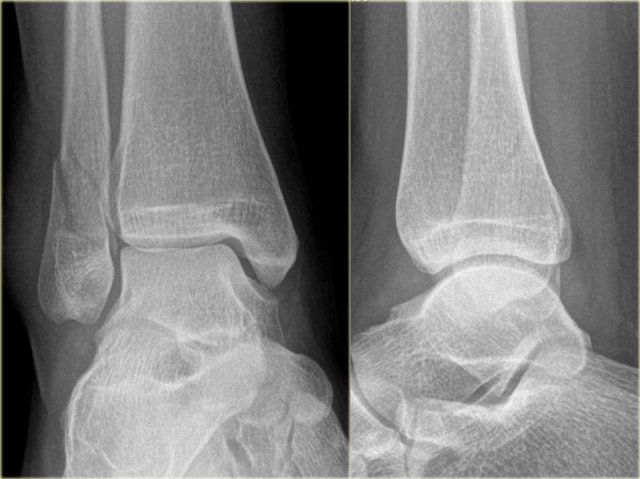

Weber-A stage I Weber-A stage I

Stage 1

The images show the usual Weber type A fractures.

These are all stage-1 fractures.

Stage-2 is extremely uncommon.

Notice the horizontal orientation of the fracture lines.

These are pull off type fractures as a result of avulsion.